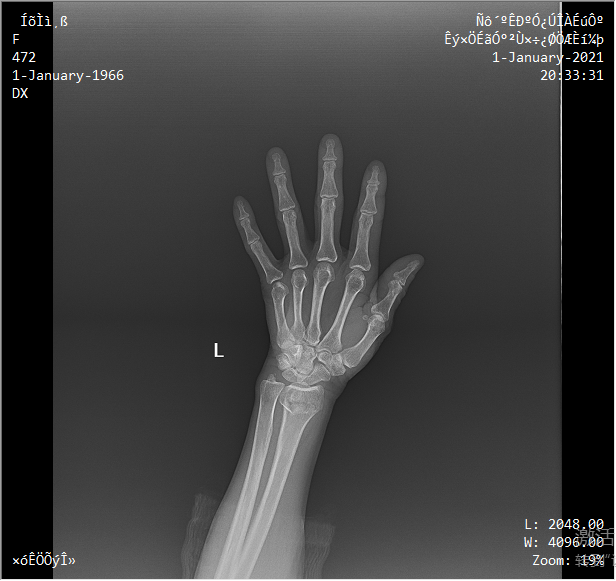

● 高效工作站系統

可選配診斷工作站,支持CT值及定位線測量等多樣測量工具。